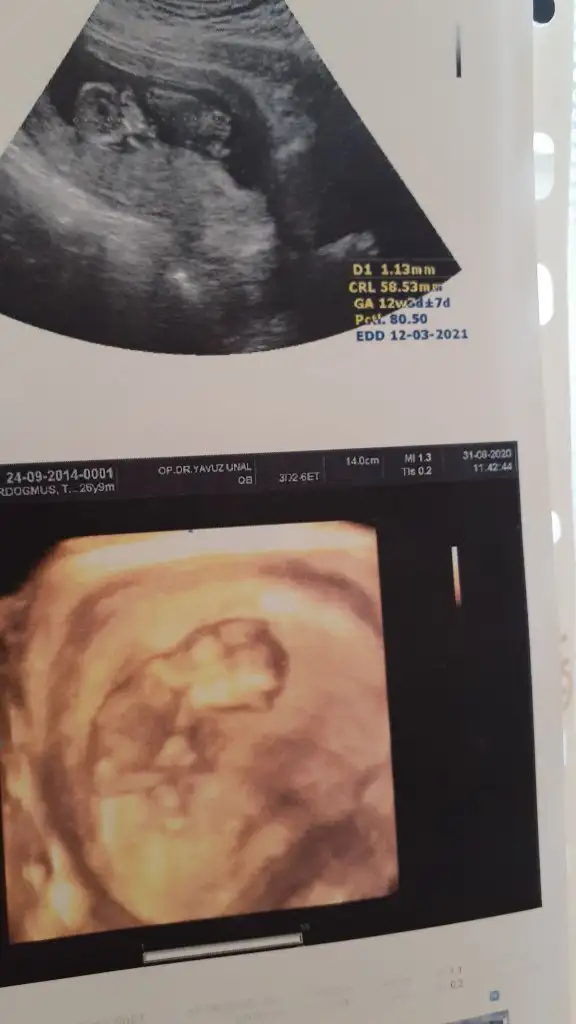

Evet tam karşıya bakıyor ama benim oyum erkek 🙈 kaç haftalık USG başka varsa paylaşın 11 12 13 haftalar olmalı

İkra bir tanem bindin ğlum olacakmış Doktor pipisini gösterdi İkra farkı işte bu yine çok mutluyum Allah'a hamd olsun Rabb'im tüm isteyenlere layıkı ile bakacak olanlara evlat nasip etsin inşallah Melyi 15 Sana da hayırlısıyla sağlıklı sından bir kız evlat dilerim canım benim